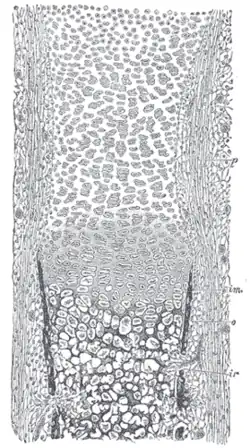

Section of fetal bone of cat. ir. Irruption of the subperiosteal tissue. p. Fibrous layer of the periosteum. o. Layer of osteoblasts. im. Subperiosteal bony deposit.

Section of fetal bone of cat. ir. Irruption of the subperiosteal tissue. p. Fibrous layer of the periosteum. o. Layer of osteoblasts. im. Subperiosteal bony deposit. -